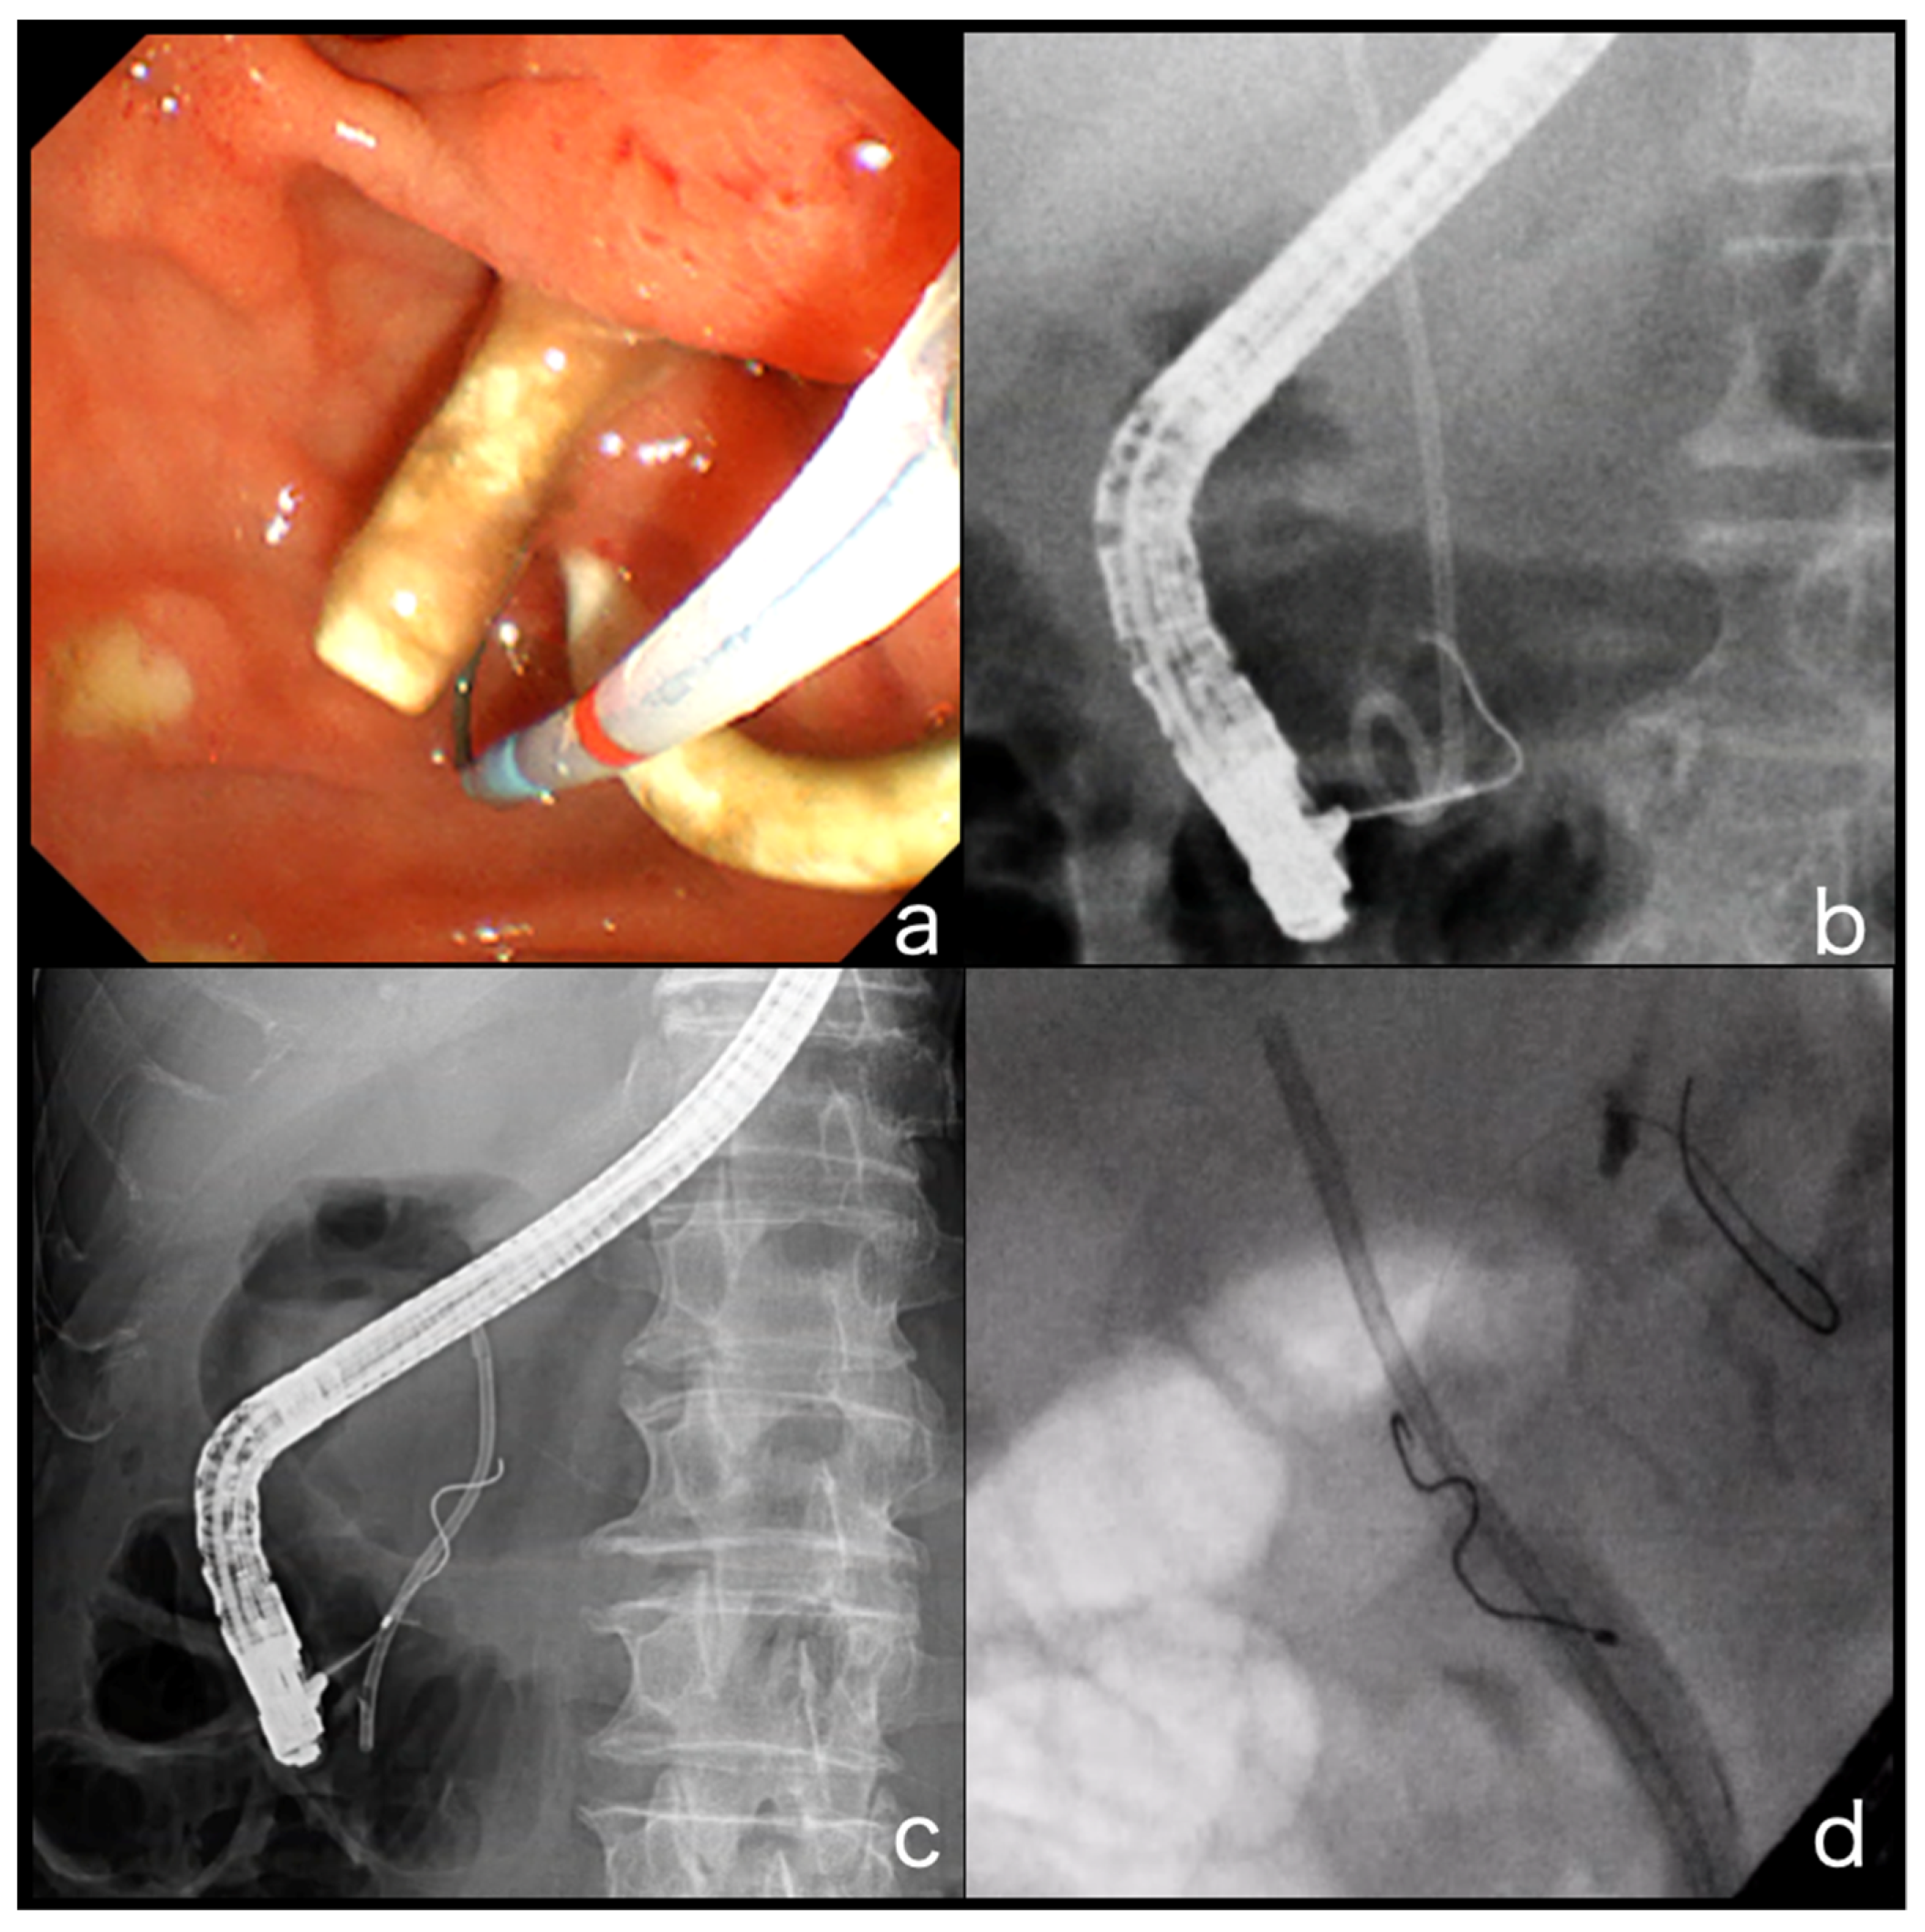

2.3. ERCP

4.1. GW Insertion into the Bile Duct Where the PS Is Inserted